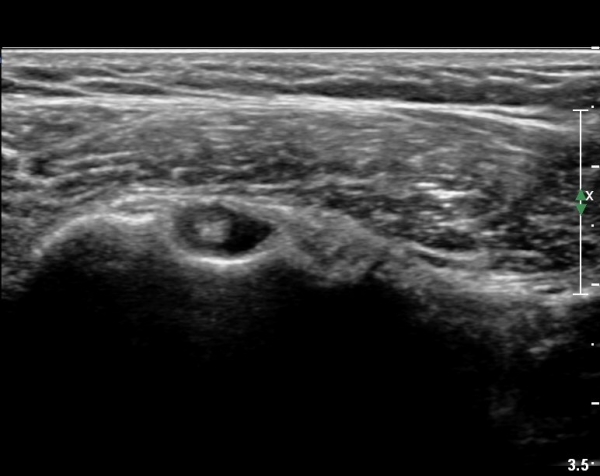

°ß°©ÇÏ±Ù°Ç Á¾´Ü¸é°Ë»ç¿¡¼­ ¼Ò°áÀý Ç¥ÃþÀÇ ºÒ±ÔÄ¢º¯È­(bone irregularity)¿Í °Ç ½ÇÁú³»

¼±»óÀÇ Àú¿¡ÄÚ À½¿°ÀÌ °üÂûµÈ´Ù(»çÁø 5).